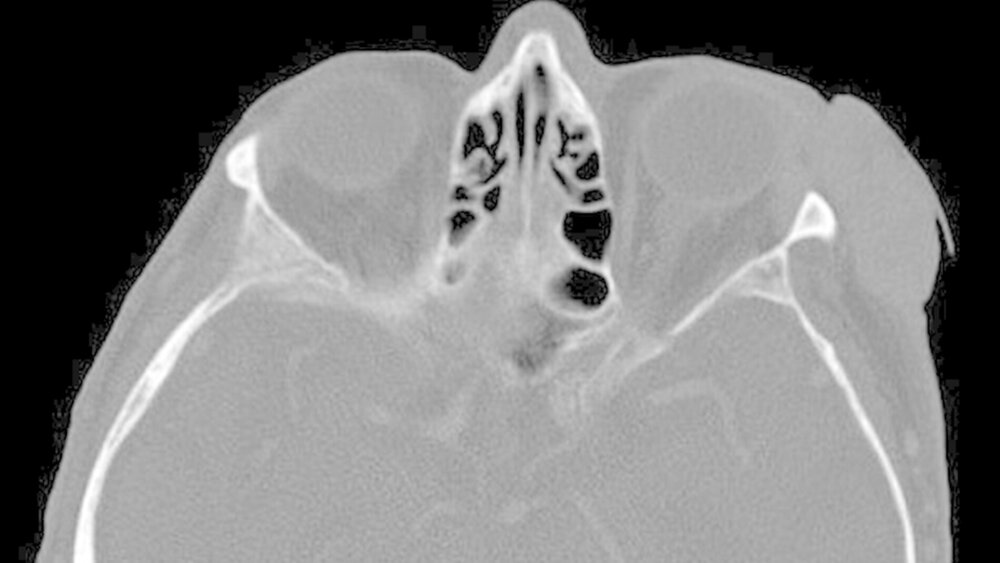

Zur weiteren Diagnostik erfolgte die Anfertigung eines Mittelgesicht-CT mit Kontrastmittel (Abbildung 2). Hier stellte sich eine lateral an das linke Jochbein angrenzende malignomsuspekte Raumforderung von 1,6 x 3,9 cm Größe ohne Hinweis auf eine ossäre Infiltration dar.

Die linke Glandula lacrimalis lag der Raumforderung direkt an, war jedoch durch eine Fettlamelle abgrenzbar.

Auch der Bulbus des Patienten war hier nicht durch den Tumor infiziert. Zervikal und im Bereich der Ohrspeicheldrüse waren keine pathologisch vergrößerten Lymphknoten darstellbar.